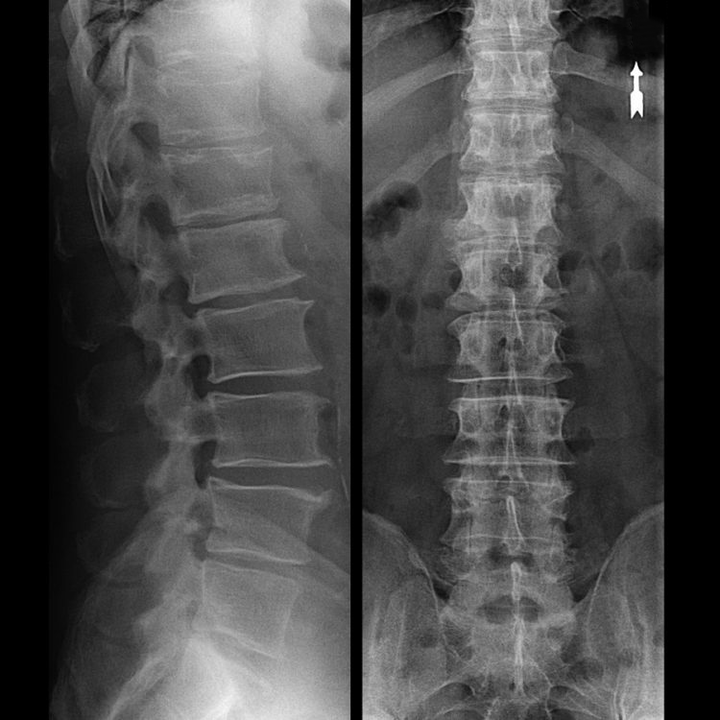

Trápaga bizkarrezurraren "X izpi" batek, eta flexio eta luzapenerako proba funtzionalak eginda ere, ez du kartilagorik erakusten, haien ehunak X izpiak transmititzen baititu. Hala eta guztiz ere, ornoen kokapenaren arabera, orno arteko diskoen altuerari buruzko ondorio orokorrak atera daitezke, lepoaren kurbadura fisiologikoaren zuzenketa orokorra - lordosia, baita ornoetan hazkuntza marjinalak egoteaz gainazaleko narritadura luzea duten orno arteko disko hauskor eta deshidratatuek. Proba funtzionalek ezegonkortasunaren diagnostikoa berretsi dezakete zerbikal bizkarrezurra.

Diskoak beraiek CT edo MRI erabiliz soilik ikus daitezkeenez, erresonantzia magnetikoa eta X izpien konputazio bidezko tomografia adierazten dira kartilagoen barne egitura eta irtenguneak eta herniak bezalako formazioak argitzeko. Horrela, metodo hauen laguntzaz, diagnostikoa zehatz-mehatz egiten da, eta tomografiaren emaitza neurokirurgia sailean hernia baten tratamendu kirurgikorako indikazio bat da, baita gaurkotasun gida ere.